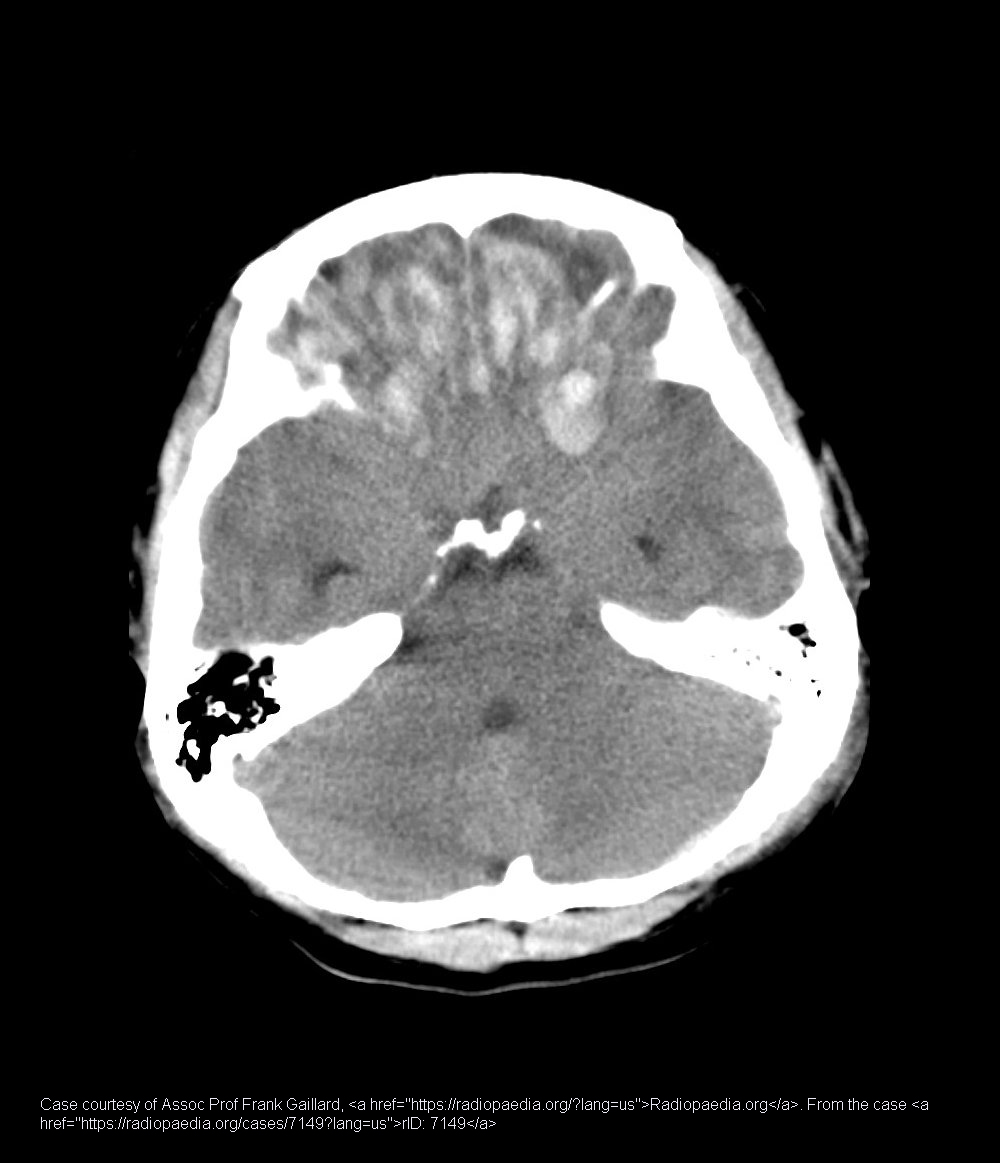

What is a cerebral contusion?

Micro-hemorrhages in brain tissue, often from coup-contrecoup injuries.

Where are cerebral contusions commonly located?

Frontal and temporal lobes.

How do fresh cerebral contusions appear on CT?

Hyperdense patches (due to fresh blood).

What symptoms might cerebral contusions cause besides imaging findings?

Headache, confusion, focal neurological deficits depending on injury location.

How can cerebral contusions progress?

They may cause swelling and increased intracranial pressure.